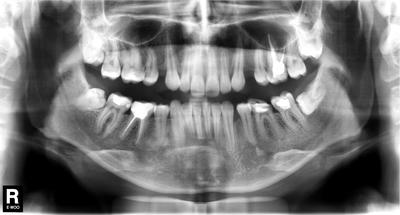

Вам сказали фигню! Вот снимок этой пациентки до лечения.

Как стоматолог, поясняю - здесь проводится ортодонтическое лечение. Явно не просто так, у пациентки были проблемы прикуса, которые привели к снижению межальвеолярной высоты. Это означает, что нижняя челюсть вывернута вверх и кпереди от своего нормального положения, что приводит к перенепряжению групп мышц вплоть до нарушения кровоснабжения головы и шеи. Кто не видит логики - постоянный гипертонус мышц пережимает сосуды. Попробуйте выдвинуть нижнюю челюсть вперед и кверху - через несколько минут заболит голова. При снижении высоты прикуса это становится хроническим, организм начинает рефлекторно сбрасывать это напряжение задействуя другие группы мышц.